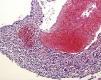

Pure renal sarcomas are rare; sometimes they are related to the renal capsule or blood vessels and a few cases of osteosarcoma have been reported. We report an unusual case of renal osteosarcoma in an 80-year-old man who underwent nephrectomy for pyelo-ureteral stenosis and hydronephrosis. The tumor was hemorrhagic and attached to the pyelocaliceal surface. Histopathology revealed a pleomorphic neoplasm with features of telangiectatic osteosarcoma. No areas of transitional or renal cell carcinoma or other sarcomatous component were present. Relevant features, such as calcifications and osseous metaplasia, were present at the implantation zone of the tumor. The present case differs from previously reported ones as it was an unexpected finding observed in a non-functioning kidney with good clinical behavior and corresponded to an unusual morphologic variant of osteosarcoma, the telangiectatic type. Finally, the relation with areas of calcification and ossification poses interesting questions as to its histogenenis.

Los sarcomas renales son raros y en ocasiones se relacionan con la cápsula renal o vasos sanguíneos. Dentro de este grupo se han descrito algunos casos de osteosarcoma. En este artículo describimos un caso peculiar de osteosarcoma renal. Un varón de 80 años fue sometido a nefrectomía por estenosis pieloureteral e hidronefrosis. Se observó un tumor hemorrágico adherido a la superficie pielocalicial. Microscópicamente mostró características histológicas propias de osteosarcoma telangiectático. No asociaba áreas de carcinoma urotelial o renal ni otro componente sarcomatoso. Un dato relevante fue la presencia, en la zona de implantación del tumor, de calcificaciones distróficas y focos de osificación heterotópica. El presente caso difiere de los anteriormente publicados. Fue un hallazgo incidental, en un riñón no funcionante, y ha mostrado buen comportamiento clínico. Histológicamente correspondía a la variante telangiectática de osteosarcoma. Por último, la relación con áreas de calcificación y osificación plantea posibles implicaciones histogenéticas.